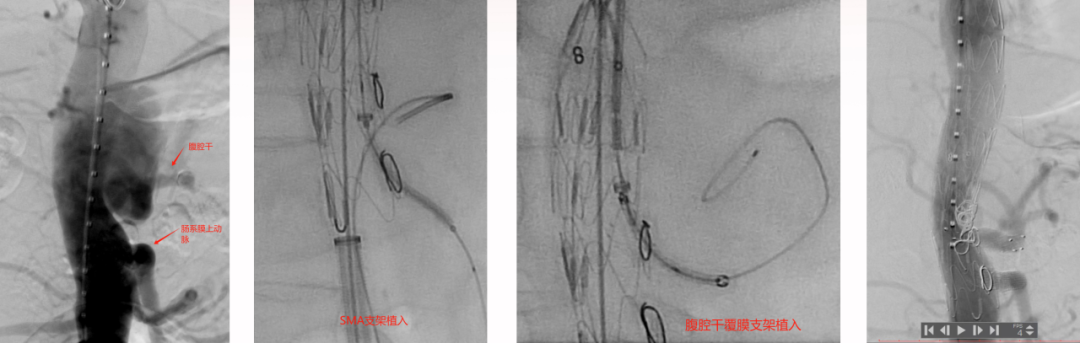

病例1 两开窗:

病例2 四开窗:

手术时间382分钟

造影剂用量320ml